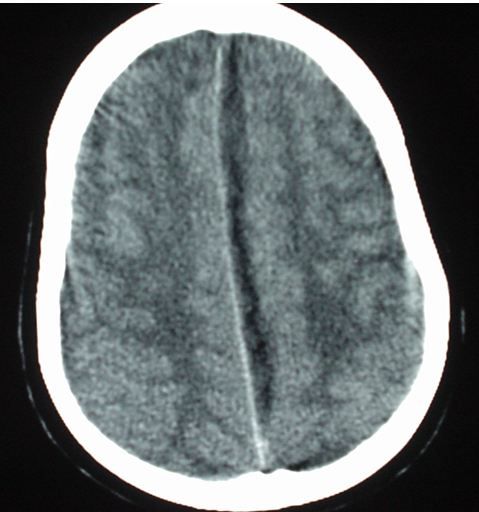

Results of a chest x-ray are normal as are those of a screening complete blood count and a metabolic panel. A CT scan of the head is performed and one cut is shown in Figure 1(please click on image to enlarge).

The radiologist is uncertain of the significance of the midline left parafalcine fluid collection, but says since there is no mass effect, you may proceed with a spinal tap.

A subdural empyema is a brain abscess in the subdural space. Like a subdural hematoma its appearance on head CT tends to be crescent shaped when on the periphery with ability to cross suture lines, however the density is similar to water and it therefor appears dark. When the location is along the midline falx the appearance is similar to the CT in this case. Subdural empyemas are less common than intraparenchymal or epidural brain abscesses but they have a tendency to progress rapidly and thus require urgent surgical drainage in most cases. See Figure2, below, showing multiple intraparenchymal brain abscesses with surrounding edema for comparison.